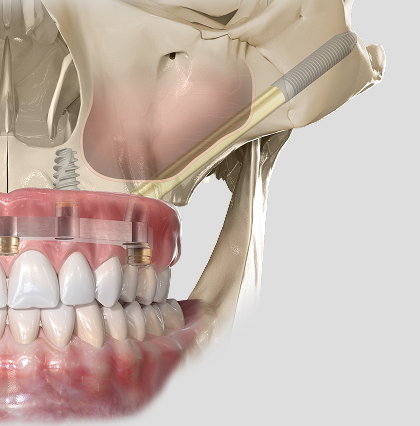

Implanty jarzmowe Zygoma

Innowacyjne implanty dla pacjentów z zaawansowanym zanikiem kości szczęki, mocowane w kości jarzmowej.

Leczenie bezzębia - bezzębie

Jest to zabieg rekonstrukcji kości części zębodołowej w bocznych odcinkach szczęk. Angielska nazwa sinus lift oznacza podniesienie dna zatoki szczękowej. Dno zatoki relatywnie obniża się poprzez zanik wyrostka zębowego na skutek przedwczesnej utraty zębów oraz tzw. ekspansję, czyli powiększenie się zatoki szczękowej. Planowane leczenie implantologiczne poprzedza wykonanie zdjęcia pantomograficznego i tomografii stożkowej CBCT.Jeżeli w miejscu planowanej implantacji dno zatoki jest obniżone, zleca się wykonanie zabiegu podniesienia dna zatoki szczękowej, czyli właśnie sinus liftu. Zabieg ten można wykonać w sposób otwarty: z bocznego dojścia poprzez przednią ścianę zatoki szczękowej deponuje się materiał kościotwórczy wraz z izolującą to miejsce membraną. Dzięki temu otrzymujemy stabilne podłoże do wprowadzenia implantu, który może być założony jednocześnie z rekonstrukcją lub w odroczonym czasie. Druga metoda, zamknięta, umożliwia precyzyjne wprowadzenie materiału rekonstrukcyjnego dla kości wąskim, odwierconym kanałem. Do każdego przypadku rodzaj zabiegu dostosowywany jest indywidualnie.